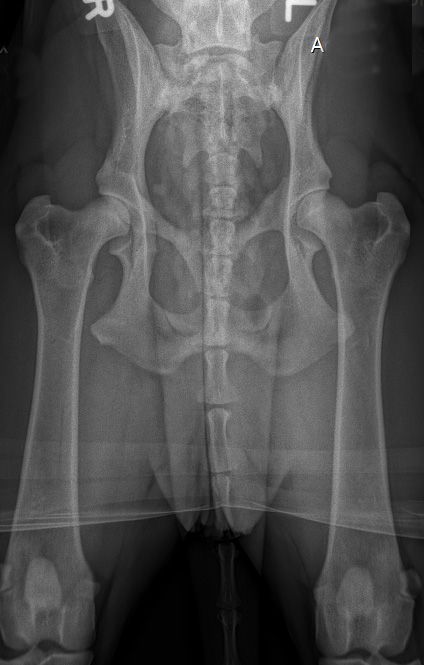

![]() HD-C/ HD-leicht/HD-2 (ab diesem Befund wird im ADRV e.V. kein Hund mehr zur Zucht zugelassen) |

![]() HD-D/ HD-mittel/ HD 3 |

C |

= Grad1 (leicht) |

HD-2 |

leicht |

Leichte Inkongruenz, divergierender Gelenkspalt, NORBERG-Winkel um 100 Grad |

D |

= Grad2 (mittelgradig) |

HD-3 |

mittel |

Gravierende Veränderungen mit arthrotischen Zubildungen, NORBERG-Winkel zwischen 90 und 100 Grad |